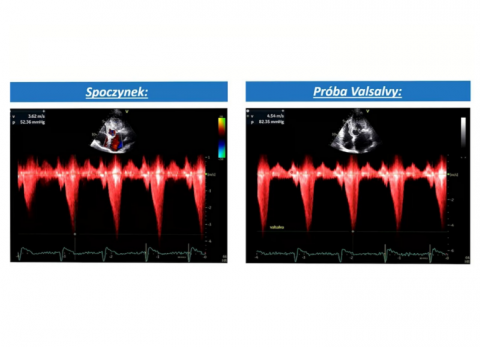

prof. dr hab. n. med. Jarosław KasprzakDane kliniczne:Pacjentka z niewydolnością sercaRozpoznanie główne:Kardiomiopatia przerostowa z zawężaniem drogi odpływu lewej komoryPoruszane zagadnie...